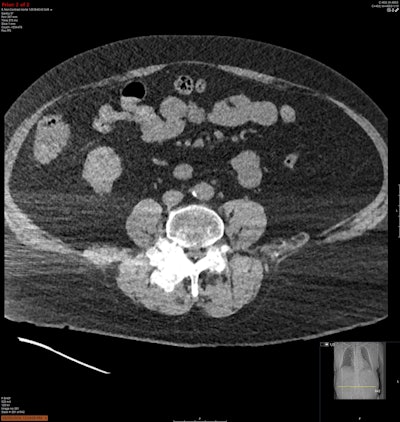

“On the CTPA and aortogram, several large calcified masses arising from the lower lumbar spine were seen almost completely effacing the L3/4 and L4/5 facet joints and causing moderate-severe spinal canal stenosis,” Zhang pointed out.

Incidental note was made of widespread destructive arthropathy and multiple calcified perivertebral masses in the lower lumbar spine, and a possible bone or soft-tissue-based malignancy causing nerve compression was raised by the medical staff. Imaging was reviewed with radiology. These changes were also found in the bilateral sternoclavicular, glenohumeral, and thoracic costovertebral joints. Prior x-rays were examined, and these changes were determined to be most likely due to tophaceous gout.

Soft tissue window of a tophus centred in the L2 lamina extending into the neural foramen.